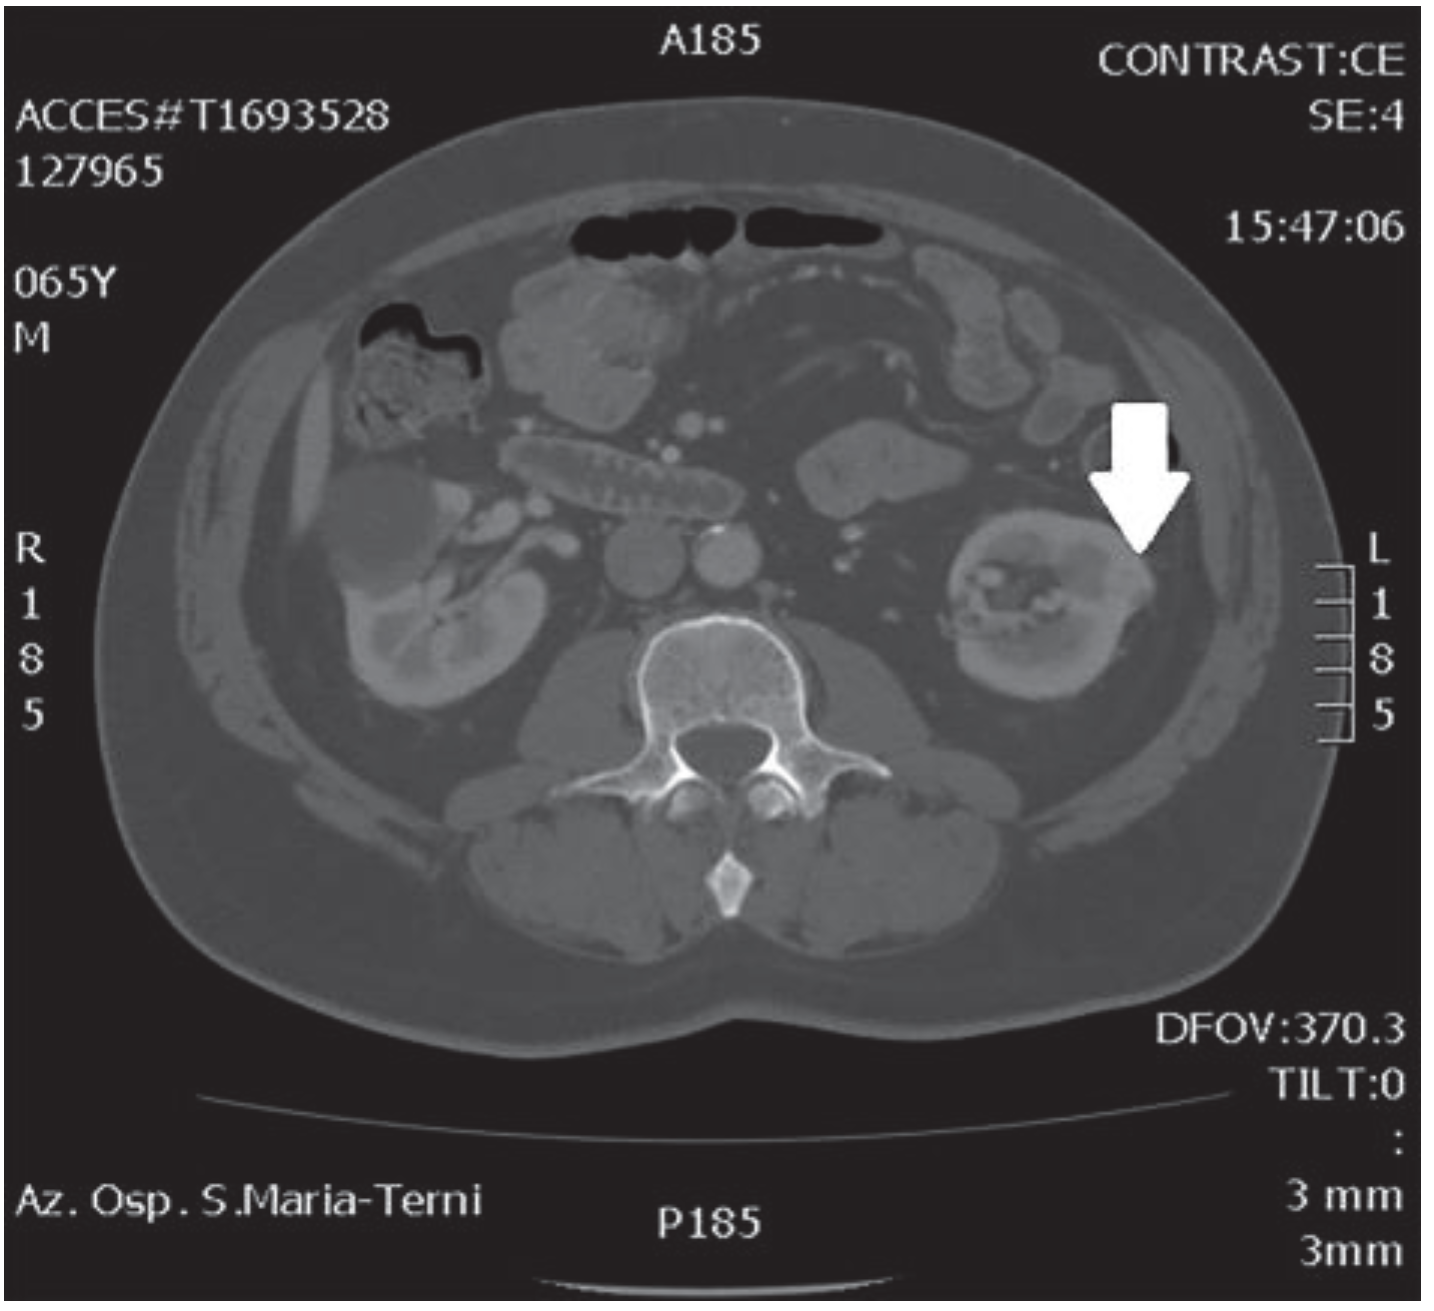

In October 2018, a 66-year-old man with hypertension and no significant prior surgical history showed a serum PSA level of 4.5 ng/mL. At clinical stage T1c, Gleason score 6 (3 + 3) PCa was diagnosed in 11 out of 22 core biopsies, all in the right side of the gland. A total body bone scan was negative for metastasis. An abdominal CT scan showed no evidence of pathologic pelvic lymphadenectomy but highlighted two incidental heterogeneous enhancing solid masses in the left kidney that were suspicious for renal cell carcinoma: one sized 32 mm in the lower pole and the second of 10 mm in the mesorenal site. A 6-cm asymptomatic simple cyst was found in contralateral kidney. Serum creatinine was 1.43 mg/dL. CT imaging of renal masses is shown in Figure 1 and Figure 2.

Figure 1.

Mesorenal mass.